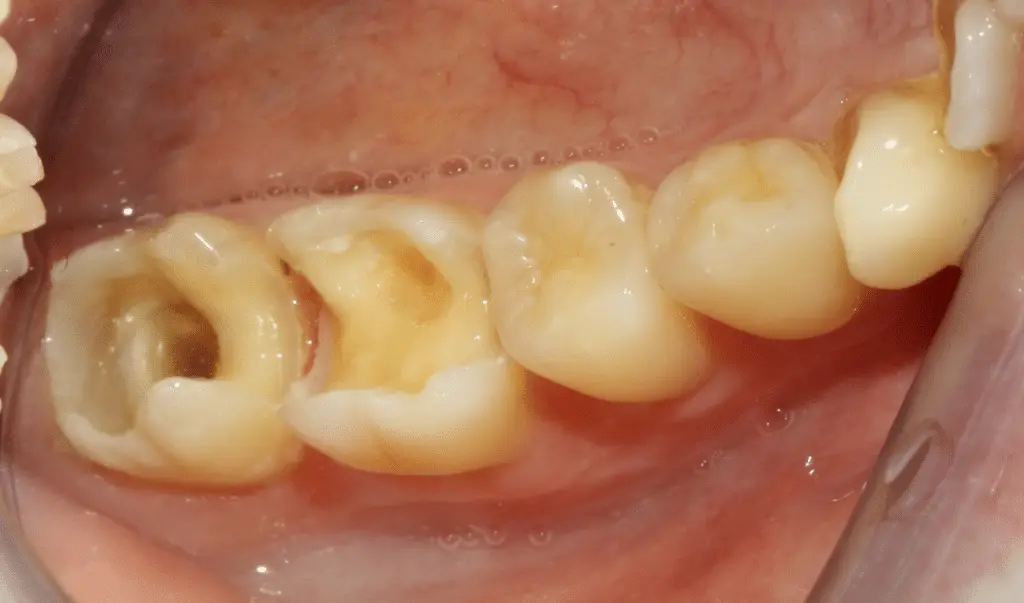

Vorbereitete Backenzähne vor dem Einsetzen von hochwertigen Keramikinlays in der Zahnarztpraxis Kassel.